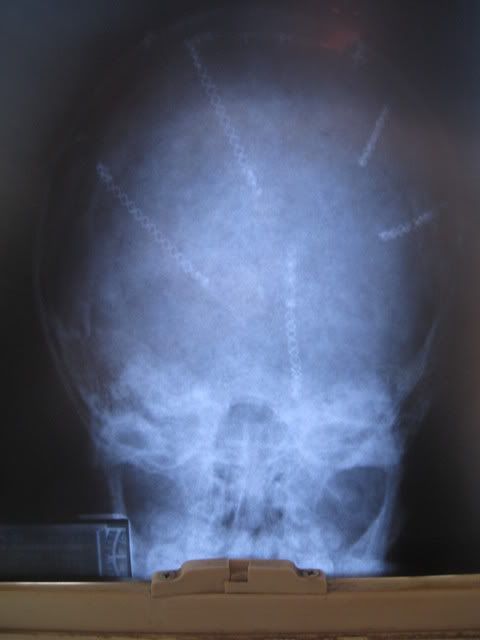

Here's the xrays. These were taken when he was 9 years old so the bone has grown over many of the 'plates' and screws.